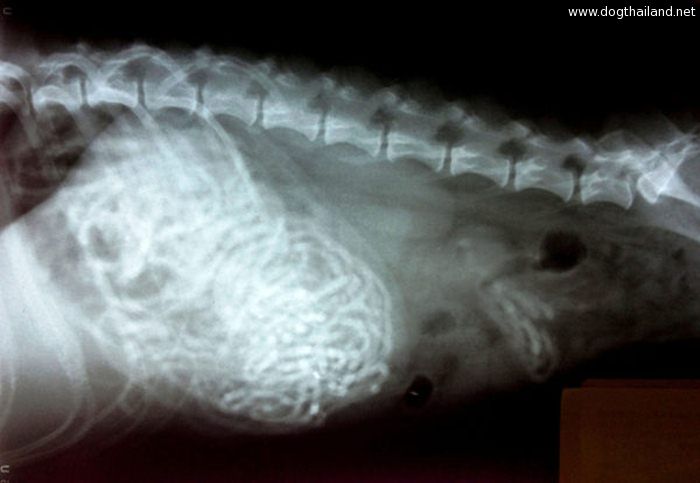

โดยทางเว็บไซต์ทเวนตี้มินูทเท็น ของสวิตเซอร์แลนด์ ได้เผยแพร่ภาพเอ็กซเรย์ภายในท้องของสัตว์เลี้ยงหลากหลายชนิดด้วยกัน ซึ่งแต่ละภาพนั้นชวนให้สยดสยองเป็นอย่างมากเลยทีเดียว

เพราะเมื่อแพทย์เห็นฟิล์มเอ็กซเรย์ก็ถึงกับผงะ และช็อคไปเลยทีเดียว จนต้องรับทำการล้างกระเพาะอาหารให้กับสัตว์เลี้ยงเหล่านี้อย่างเร่งด่วนทันที เเนื่องจากในกระเพาะของสัตว์เลี้ยงเหล่านี้เต็มไปด้วยสิ่งแปลกปลอมมากมาย ที่ไม่น่าเชื่อว่า "จะกินได้...?" นั่นเอง จะมีอะไรบ้าง ไปดูกันเลย

5. ภาพเอกซเรย์ภายในท้องของสุนัขตัวหนึ่ง ที่มี "ถุงเท้านักเรียนมากถึง 43 คู่"